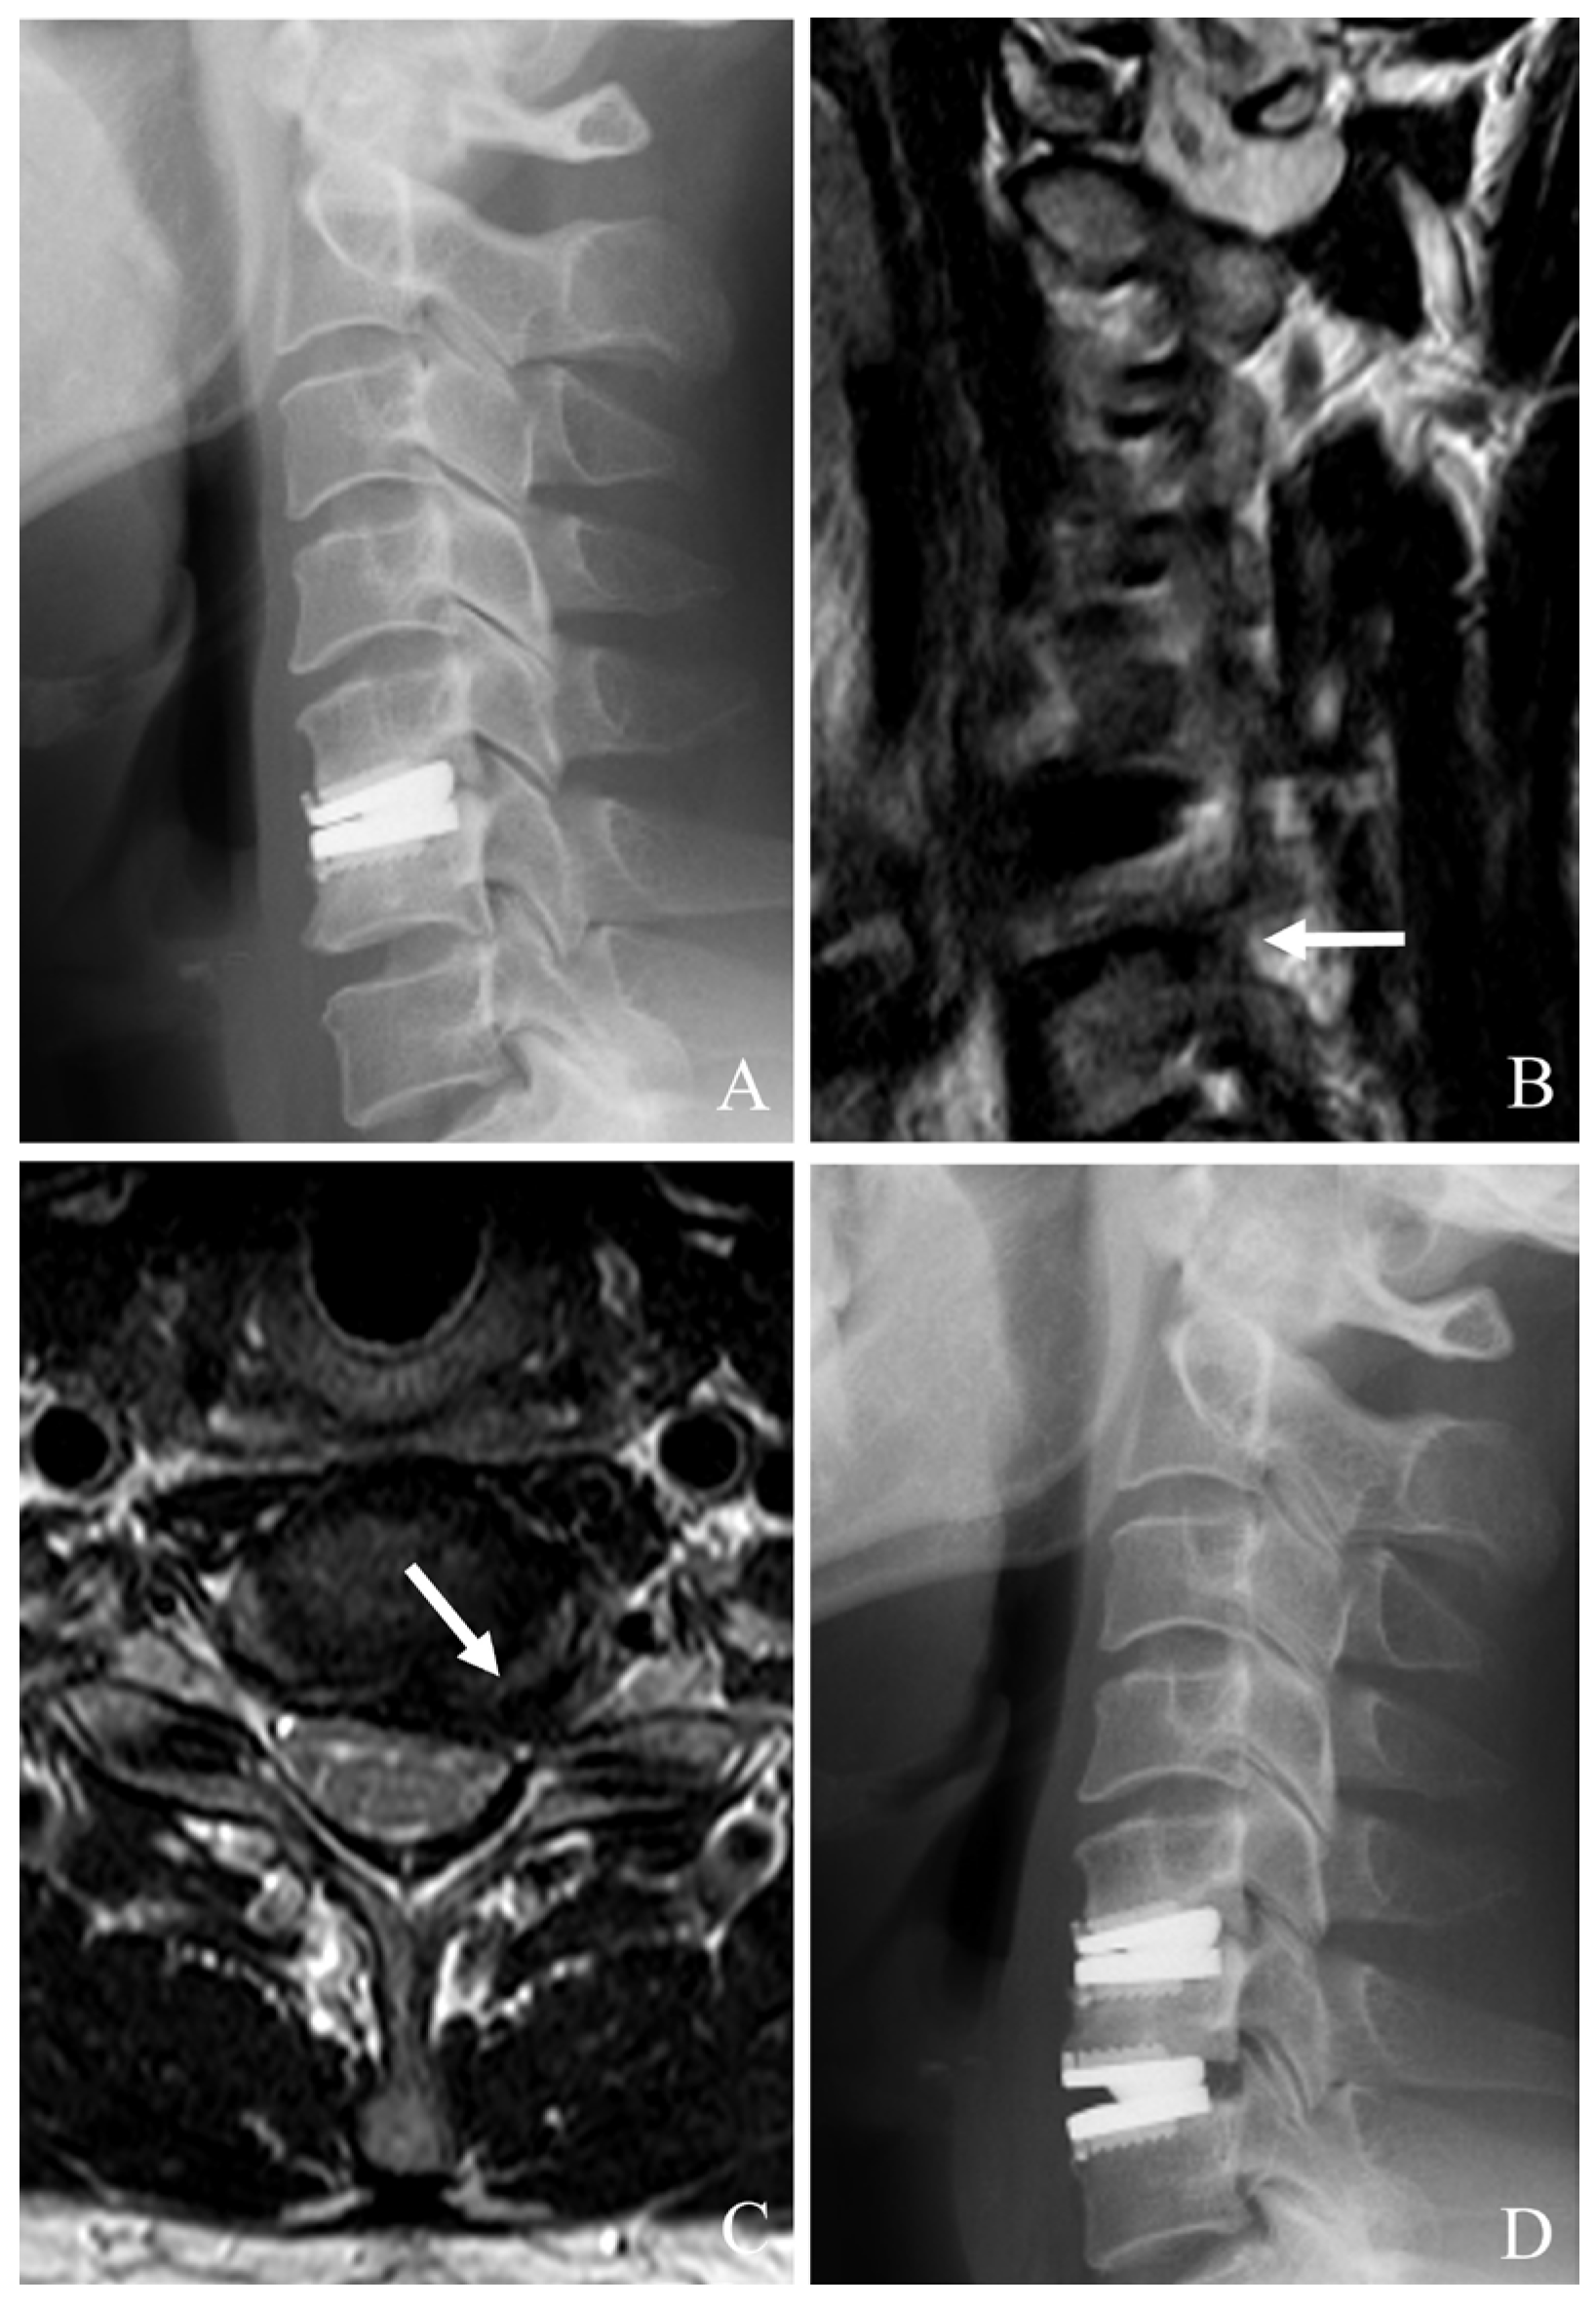

Conversion to ACDF is the most common approach when index-level failure is associated with severe heterotopic ossification (HO), significant subsidence, or mechanical instability [22,23,24,25,26]. This method involves an anterior approach to remove the failed prosthesis, debridement of scar tissues and HO, and neural decompression such as posterior longitudinal ligament (PLL) resection and uncoformaminotomy. An interbody fusion is then performed using appropriate graft material, augmented by anterior plating to achieve stability. ACDF provides robust stabilization and high fusion rates (often >90%). It can reliably alleviate symptoms (Figure 1). However, it sacrifices motion at the index level, potentially predisposing patients to further ASD.

Figure 1. Plain X-rays (A,B), magnetic resonance image (C), and computed tomography (D) showing cervical disc arthroplasty at C5–6 and C6–7 with severe foraminal stenosis and posterior osteophytes (white arrows). The patient underwent removal of C5–6 and C6–7 prosthesis and revisional anterior cervical discectomy and fusion (EH).